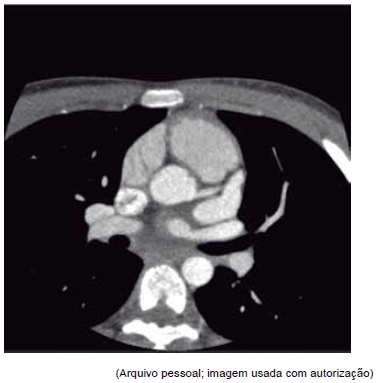

Este corte tomográfico pode ser compatível com qual diagnóstico?